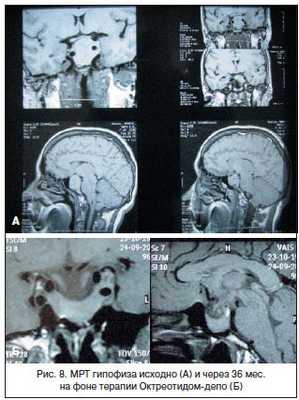

От предложенного нейрохирургического лечения отказалась, были назначены аналоги соматостатина длительного действия (Октреотид-депо, производитель «Фарм-Синтез», Россия), которые получала с августа 2005 по февраль 2006 г. в дозе 20 мг 1 раз в 28 дней. На фоне лечения: СТГ базальный - 24 мМЕ/л (-31% от исходного), ИРФ-1 - 453 нг/мл (101-267) (-47% от исходного) (рис.3,4); ТТГ, Т4 св. - без динамики. Также отмечалось клиническое улучшение в виде снижения частоты и интенсивности головных болей, уменьшения потливости и отечности лица. Выполнена МРТ головного мозга: эндо-, инфра-, супралатероселлярная макроаденома гипофиза 17*19*28 мм (суммарный объем - 4,33 см3, уменьшение на 44% от исходного объема).

У пациентки, несмотря на отсутствие полной «биохимической» ремиссии заболевания, отмечена выраженная положительная динамика размеров опухоли, сопровождавшаяся регрессией клинических симптомов (рис. 5, 6).

Данный клинический случай демонстрирует выраженный туморосупрессивный эффект аналогов соматостатина длительного действия даже без достижения полного «биохимического» контроля над акромегалией.